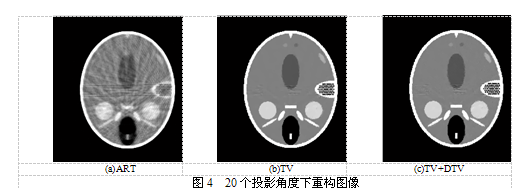

由图3不难看出,30个投影角度下,ART重建结果最差,出现诸多伪影,边缘处也较为模糊。而TV与本文算法之间整体上没有太大差异,但边缘处本文算法较TV算法更为清晰,内部均匀性上TV算法则略有优势。为进一步比较算法在更少的投影数据下的重建情况,我们在20个投影角度下进行重建,迭代次数依然是ART和TV均1000次,本文算法首先用TV方法迭代800次,再用DTV迭代200次,重建结果如图4所示。显而易见,图4所示重建结果质量均较图3有所降低,这说明随着投影数据的减少,重建结果有所下降,但相同条件下,本文算法依然是最优的,不仅边缘细节保持良好,内部ROI区域灰度分布也很均匀。

表1给出了前述30个投影角度下(30 Projection)和20个投影角度下(20 Projection)两组实验重建结果的RMSE与UQI。从表1可以看出,在20个投影角度下所有方法重建图像RMSE都超过在30个投影角度下所重建图像,而UQI则均小于在30个投影角度下所重建图像,这与图3、图4所示相吻合,说明投影数据的减少对所有重建算法均有影响,重建质量都略有下降。无论投影数据如何,TV+DTV算法重构所得RMSE小于ART和TV算法,UQI则大于ART和TV,说明整体上本文算法重建效果最佳,重构后图像与原始图像更加吻合。需要指出的是,当迭代数较少时,对角TV相对于传统TV并无显著优势,且在抗噪性能上仍有待提高。